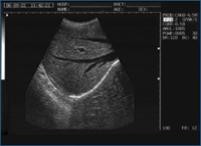

Galería de Imágenes Clínicas

Sonolife 9618